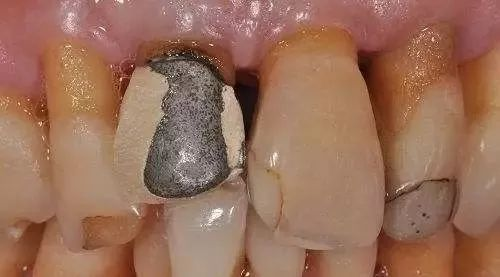

图片

烤瓷冠的崩瓷问题